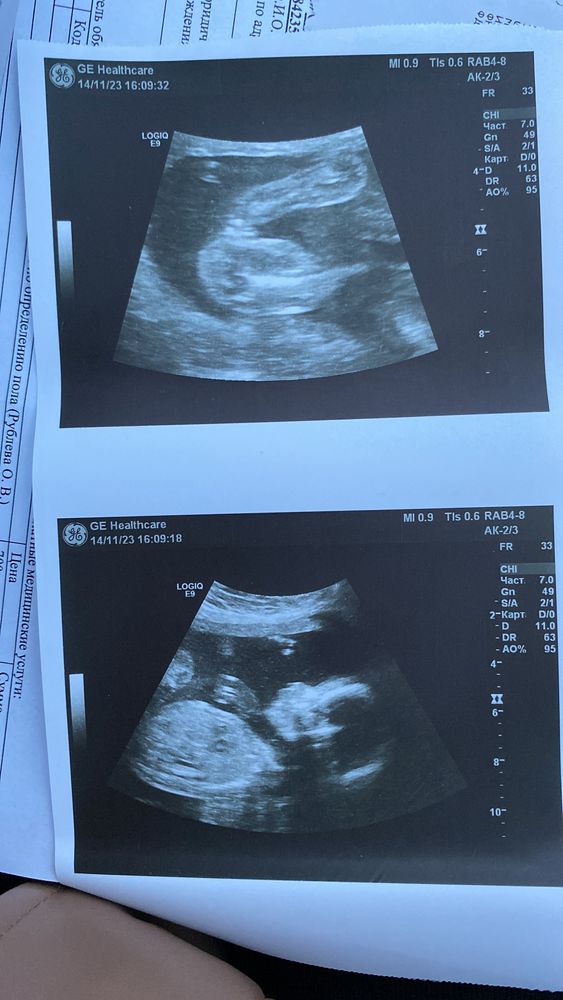

Определение пола по фото узи

Здравствуйте. Подскажите пожалуйста, кто у нас по фото? 18 недель Изображение

15.11.2023

Тоже кажется, что девчуля это)